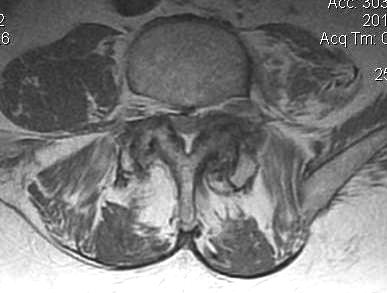

B. Axial slices

Findings

- no fat about dura

- trefoil shape canal

- lateral recess or foramina compression

- nerve root compression